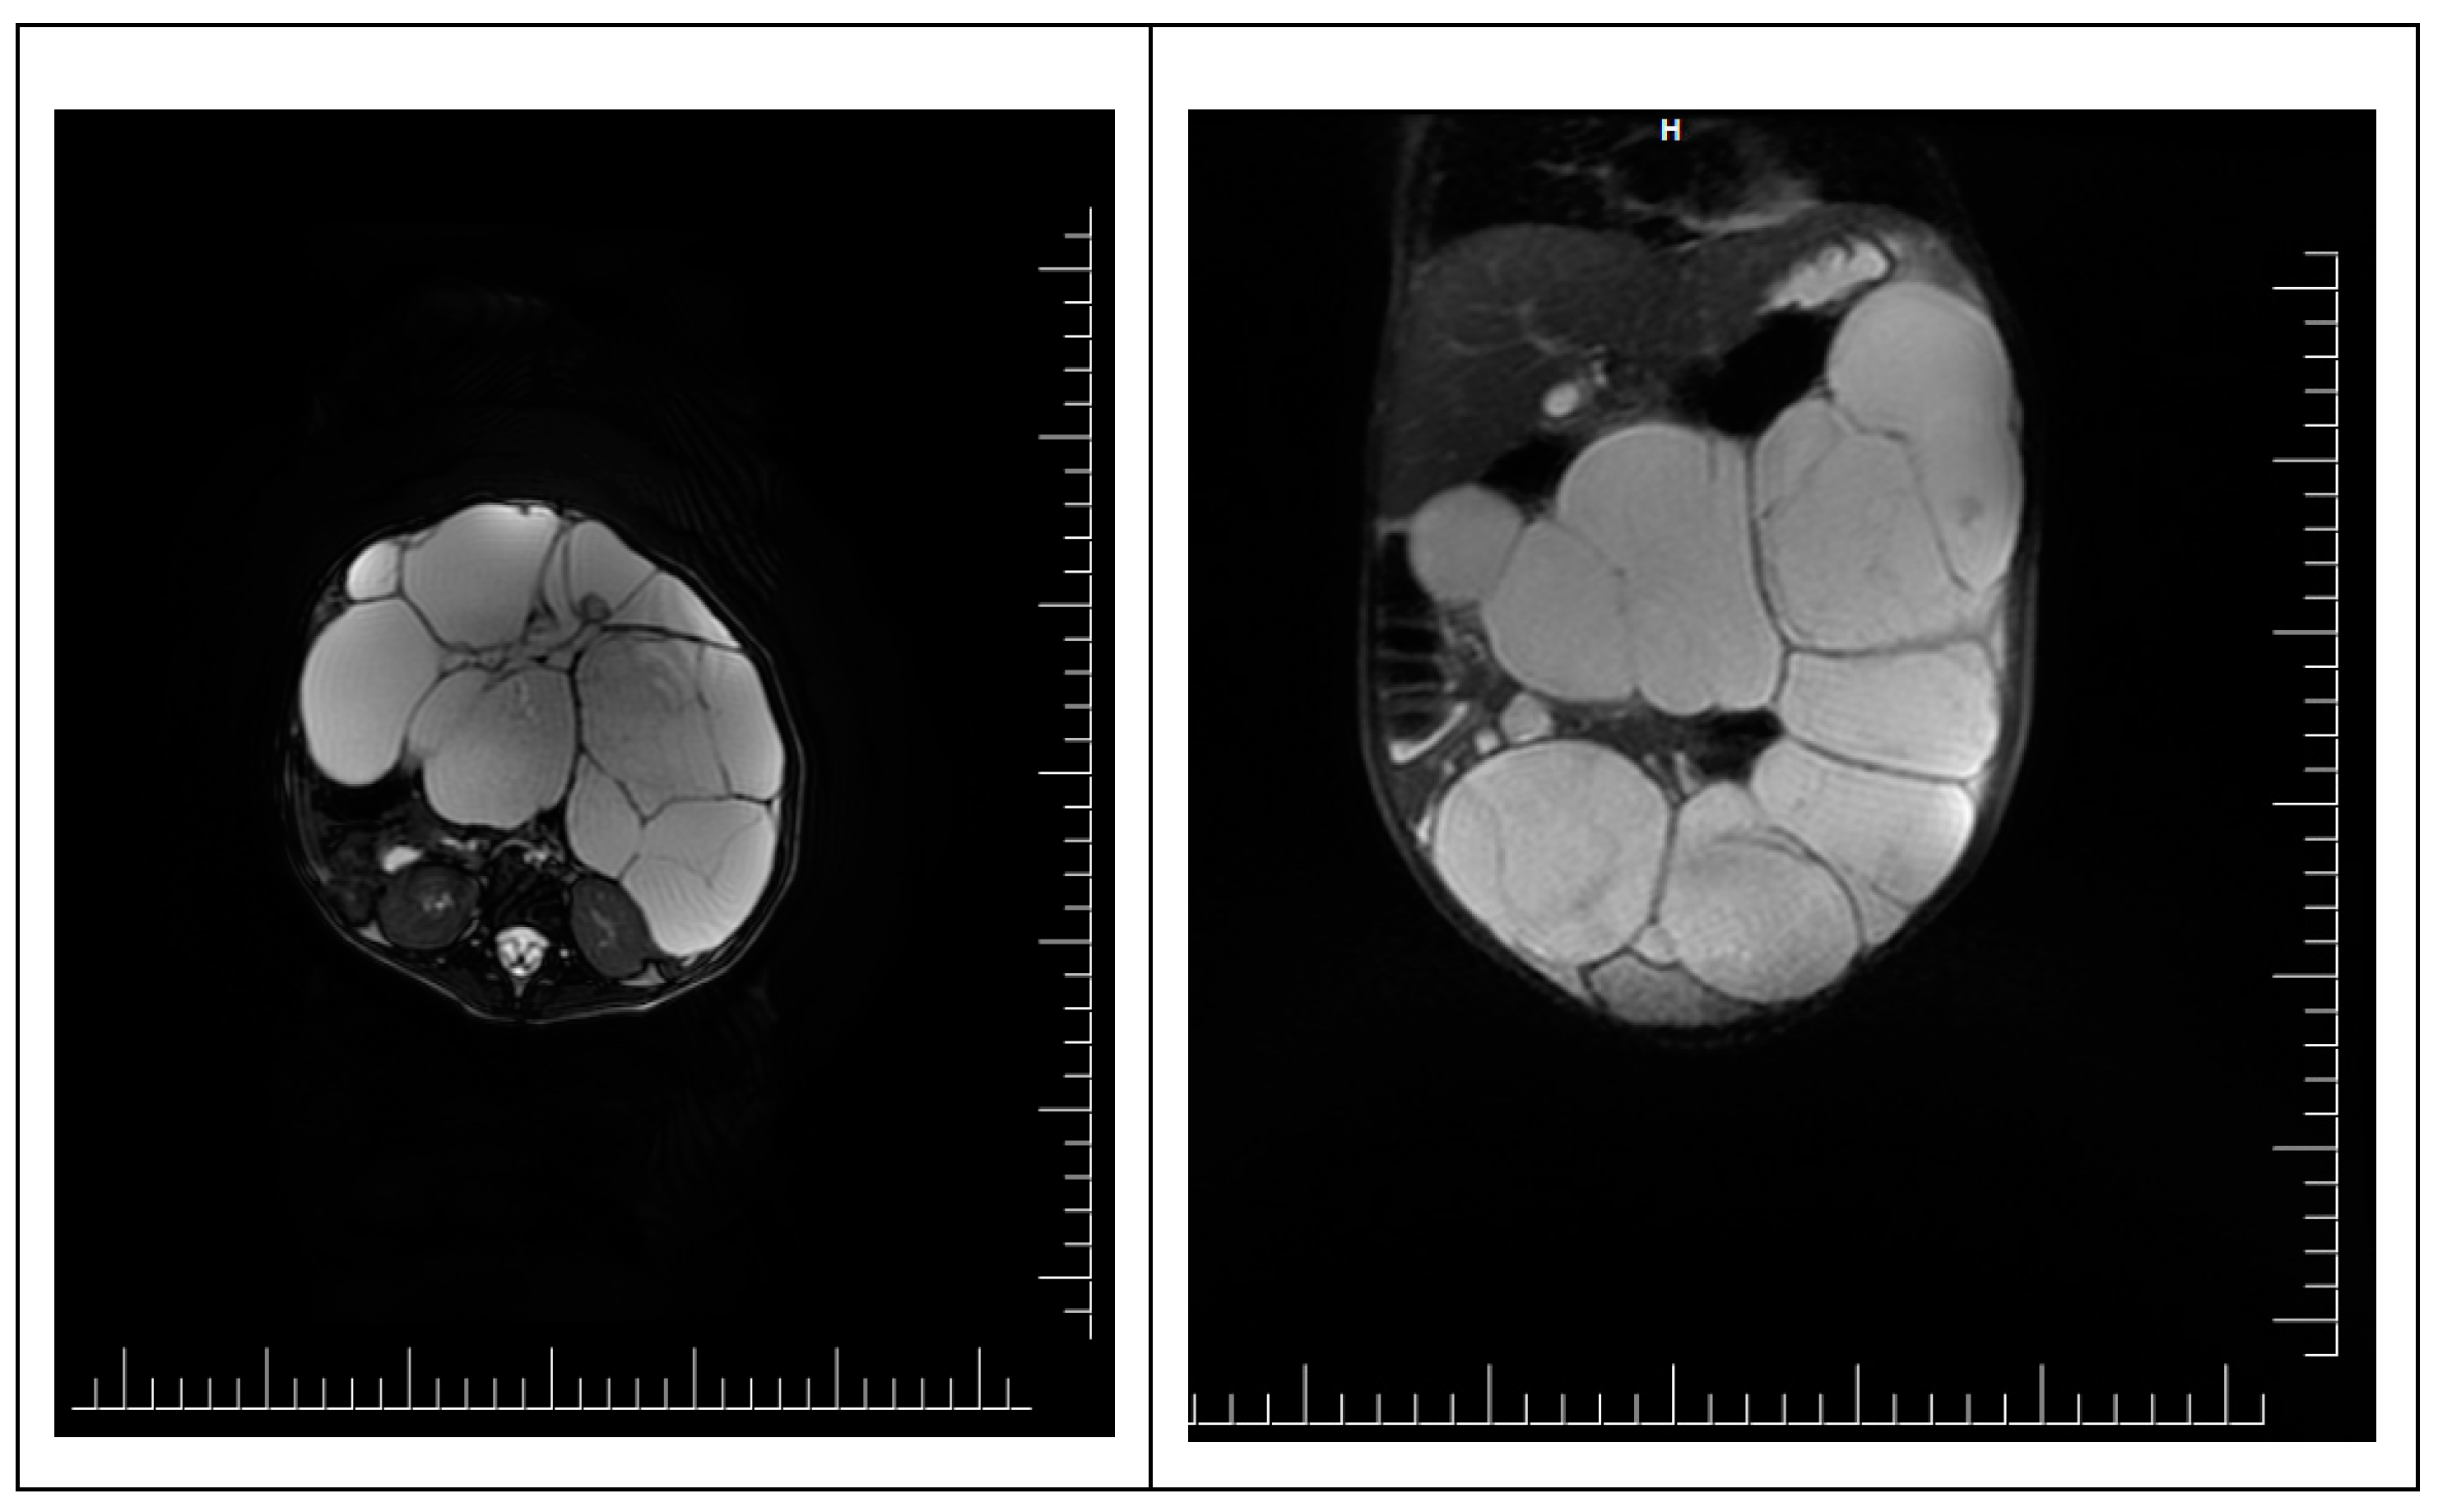

To accurately specify the diagnosis, an abdominal pelvic MRI was performed. It shows a voluminous abdominal-pelvic cystic expansive formation, with convex contour, relatively well delimited by a thin wall, multiloculated, multiseptate, with moderate parietal gadolinophilia and at the level of the septa, partially altered content due to the presence of areas with intermediate T2 signal, with dimensions of approximately 86/157/230 mm [AP/T/CC]. The described formation presents the following reports:

Ovaries are challenging to visualize, imprinted by the formation described—the uterus without expansive formations. The urinary bladder was examined in fullness, regular parietal contour, and homogeneous liquid. Liver with an anteroposterior diameter of the right lobe of ~ 117 mm and the lobe left ~ 65 mm, with a homogeneous structure without focal lesions. Undilated intra-/ extrahepatic bile ducts. The cholecyst is dilated, a wall with average thickness and liquid content, without stones. The spleen has a 74 mm diameter and a homogeneous structure. Pancreas, adrenal glands, and both kidneys, with normal M.R.I. appearance. Intraperitoneal liquid with a maximum thickness at the pelvic level of 10 mm. Without abdominal and pelvic adenopathy. No suspicious bone lesions were noted (Figure 2).

Figure 2. MRI scan of intrabdominal mass. Chistic masses in close relation to intrabdominal structures are observed. However, on an MRI scan, no involvement of the intrabdominal structures is observed.